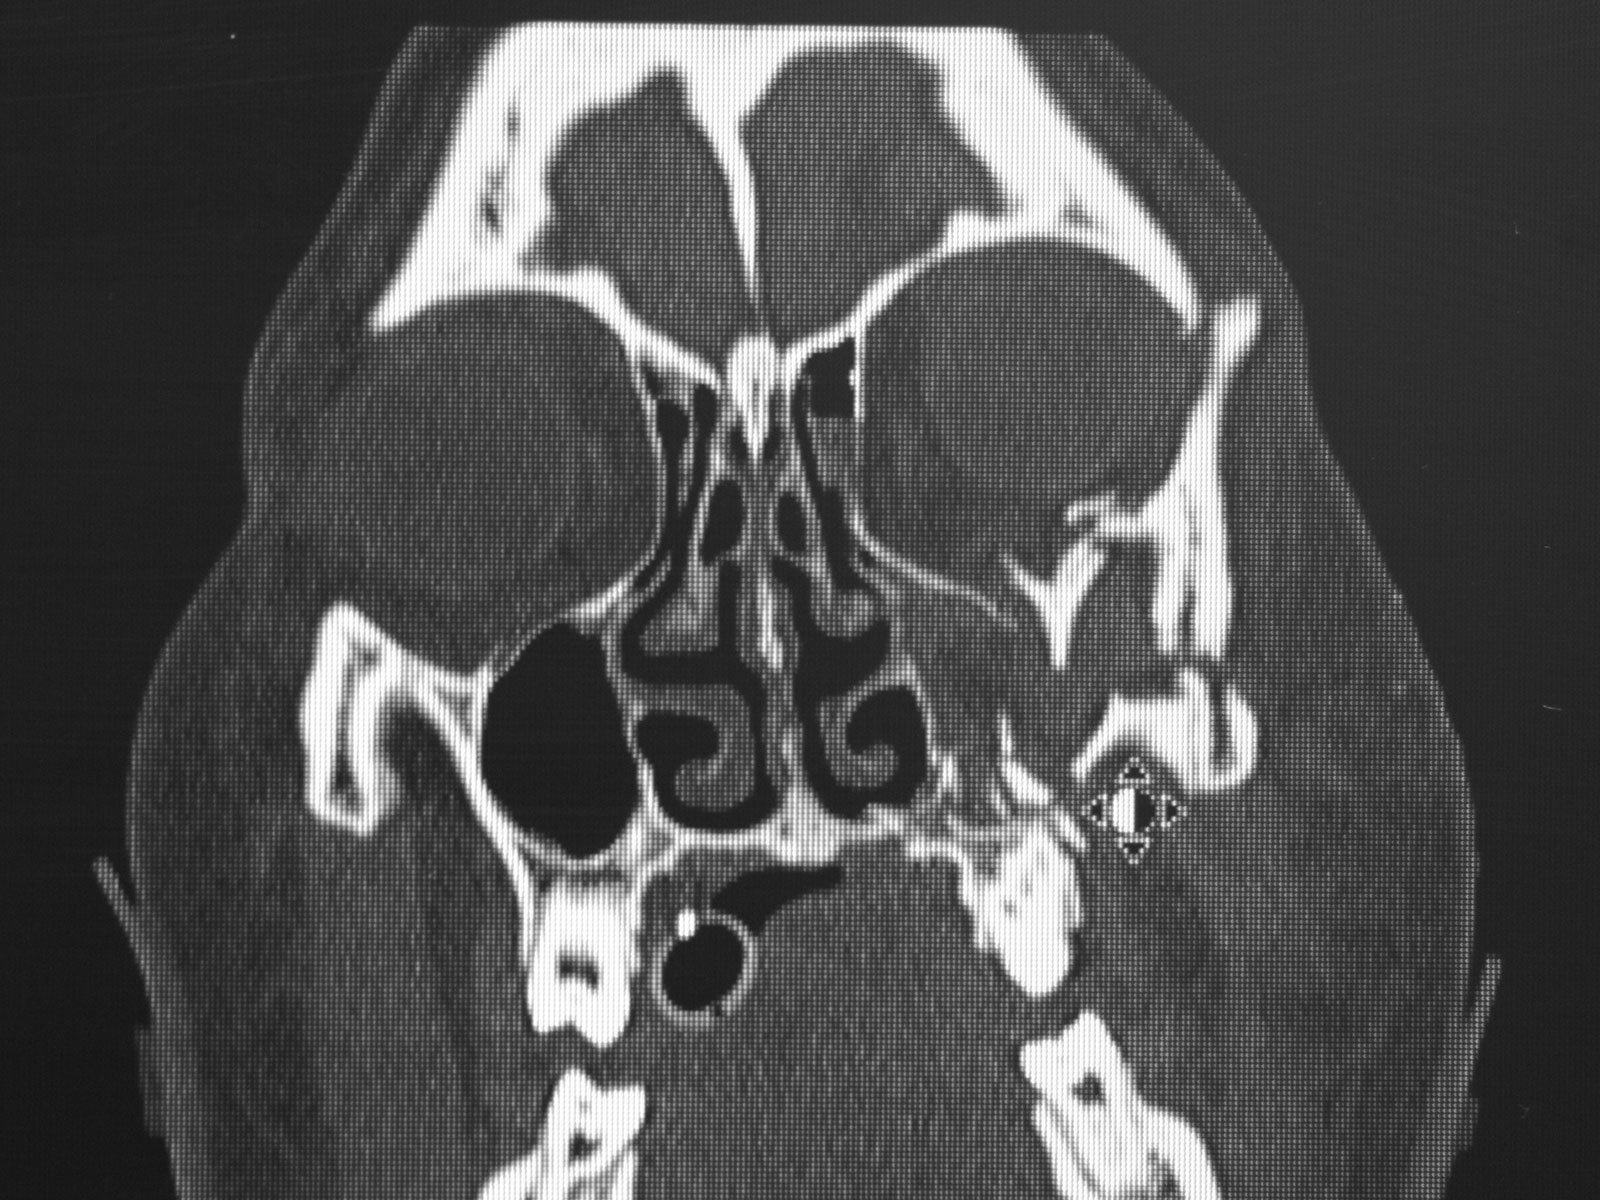

I underwent a number of procedures, the first occurring the day of my accident, to correct severe damage to my face. As Dr. Ulloa put it my face was, 'in a million pieces.  At one point there was even some bone that had lodged in my eye. He was able to address this and ended up saving my eyesight, along with reconstructing my facial features.

The photos on this website are from real surgeries performed by Dr. Ulloa. Due to the

graphic nature of the images and content, viewer discretion is advised.

Click to enlarge images